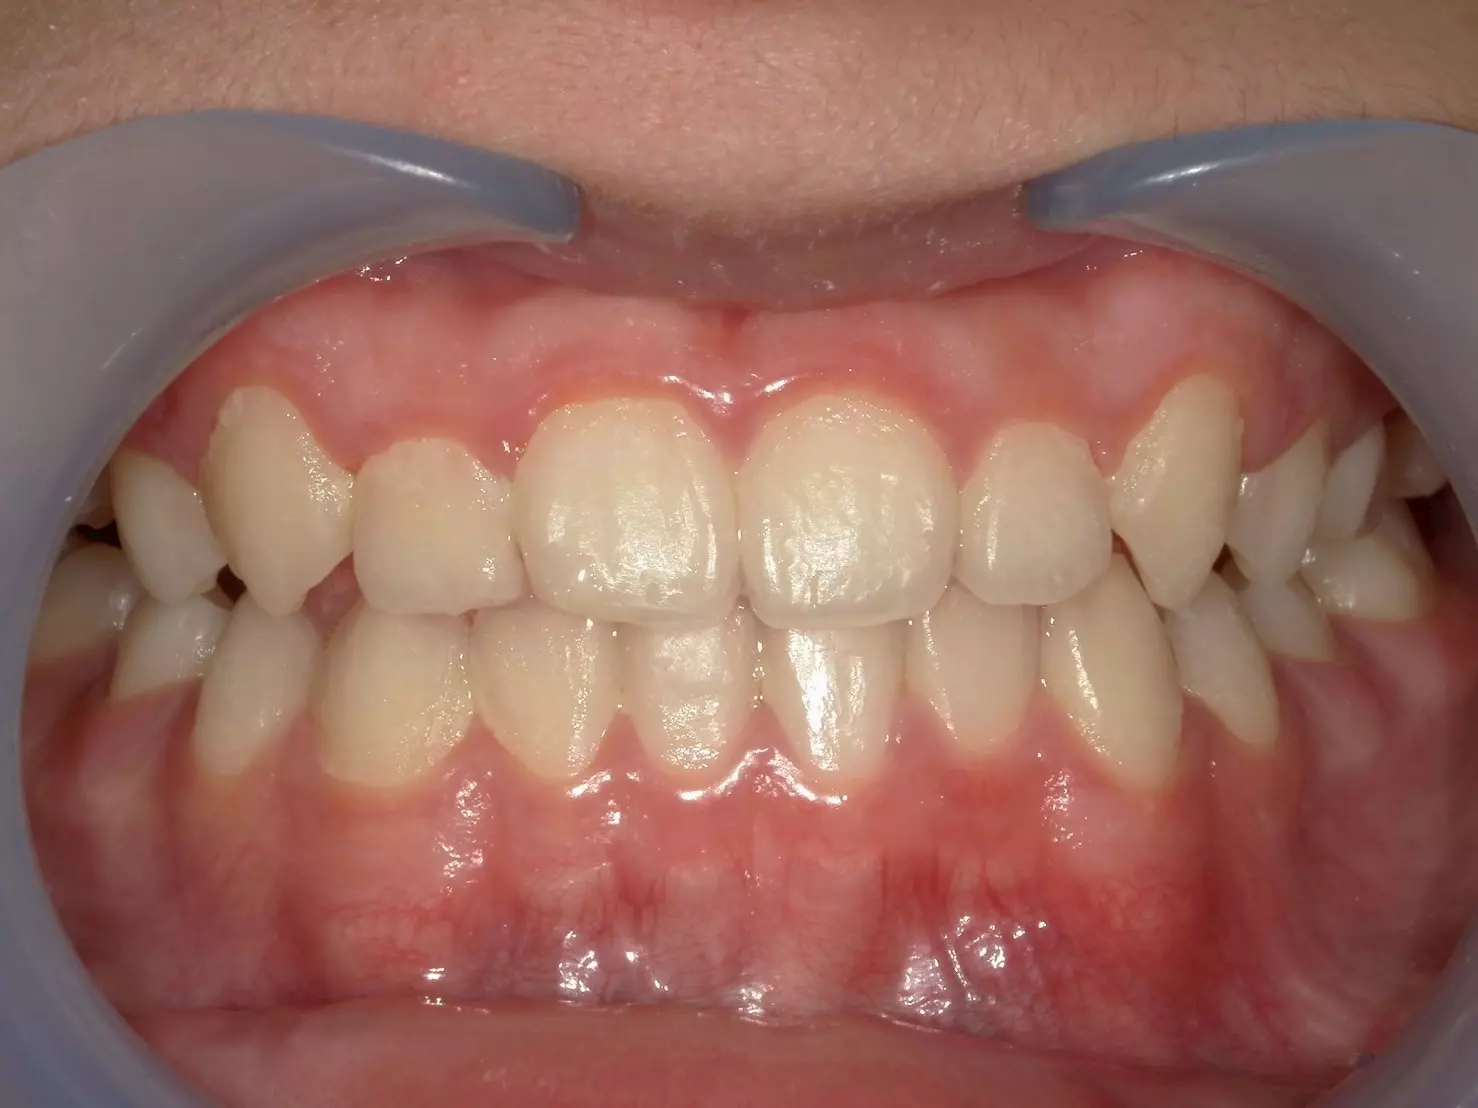

↑治療前

這位 11 歲的男孩,因為前牙錯咬問題導致上顎的牙弓變窄,前牙空間不足,不僅影響到進食,連笑容都變得不自然。他的父母觀察到,孩子不太喜歡吃東西,也漸漸在笑的時候變得保守,甚至開始避免拍照。

經過仔細檢查後,我們確認他屬於功能型第三類咬合異常 (Functional Class III)。這和大家熟知的「骨性戽斗」不同,他的狀況主要是因為牙齒排列影響了上顎的發育。這類型的咬合異常,如果沒有及早治療,可能會影響上顎的生長空間,進而讓整體顏面外觀及咬合狀態惡化。